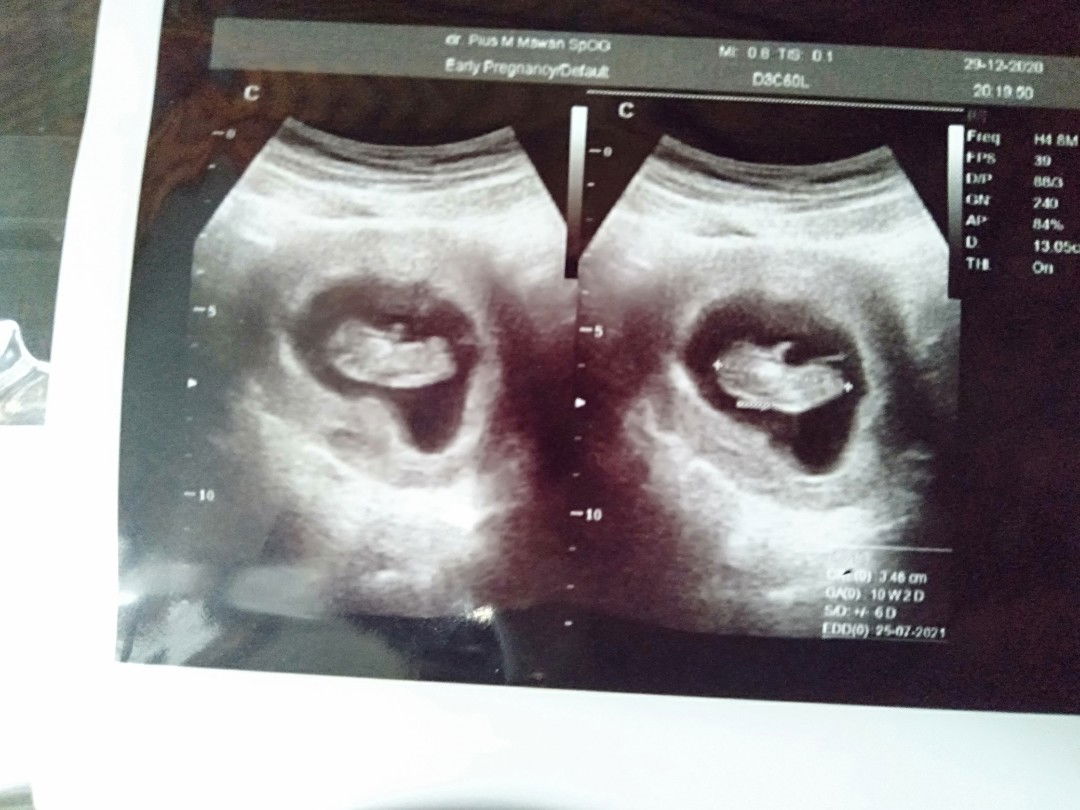

Assalamualaikum bunda2, mohon maaf saya ingin bertanya. siapa tau ada solusi untuk menghentikan diare diusia kandungan 12 Minggu. Agar tidak meminum obat. Mohon bantuannya bunda πŸ™πŸ» #bantusharig